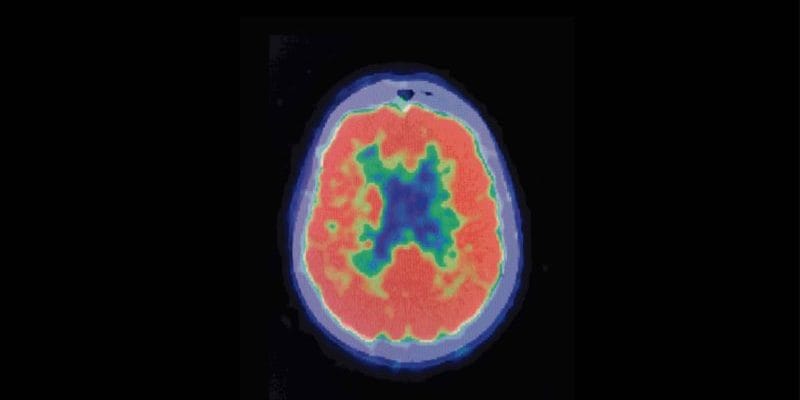

Understanding dopamine and how the brain gets “hijacked” by addiction

Do you know what is like to be distracted by something so much that it was hard for you to stop looking at it? Pre-occupied with hunger and unable to focus on anything but your growling stomach? Stuck in your thoughts about a relationship? Ever just want to “change the channel” but you couldn’t? Yes? Multiply that feeling by 10 or 100. Heroin addiction is like that, it “hijacks” the reward center of the brain. Think of it this way, eating a meal or being with someone you love feels good, right? Well, just imagine that good feeling . . . now multiply it times 10 . . . now times 100. Imagine how great that would feel.

That’s what using heroin can feel like to an addicted person. Using the drug elicits extreme and temporary pleasure. It also elicits extreme and lasting mental pre-occupation.

For a heroin addict, the pursuit of that pleasure becomes all-consuming. As a result, pleasure-chemicals supercharge certain brain connections, while the connections between good judgement and behavior become much weaker.

The Defensive Brain

As addiction takes hold, the thinking part of the brain gets pre-occupied with obtaining the “super-pleasure” provided by the drug. The addicted brain responds to the idea of cutting back or quitting the drug as a threat to survival. The using brain quickly dismisses the idea, rationalizing and justifying reasons for continued use. The brain crafts excuses, making continued drug use seem like the right thing to do. Addicts still think. It is just that the thinking and problem-solving part of the addict’s brain becomes more and more driven to figure out how to keep using the drug, no matter what. Eventually, the obsession with using takes over all the brain’s resources.